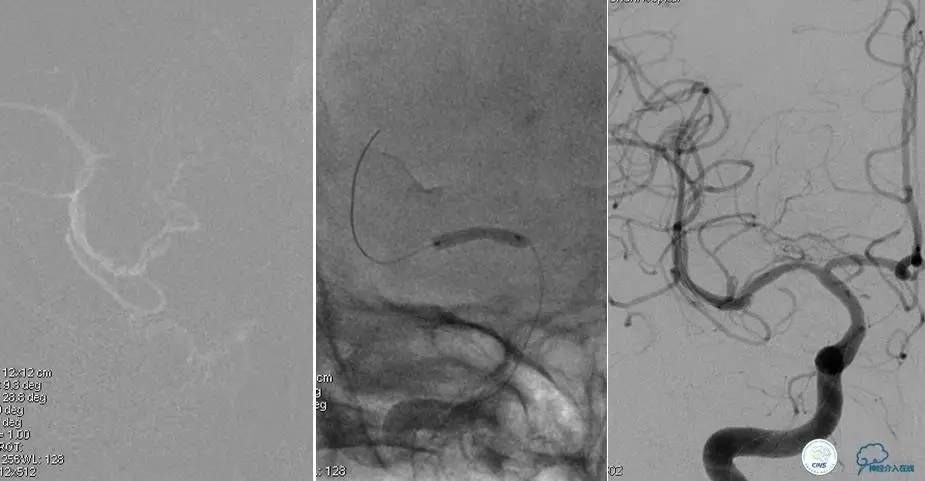

造影评价血管、判断闭塞段,微导丝小心穿过闭塞段,微导管造影,交换技术,球囊扩张,Enterprise支架。在后扩张时导丝刺破M3段血管,蛛网膜下腔出血(SAH)。

微导管进入破裂血管,栓塞弹簧圈1枚,出血停止,结束手术。继续双抗,术后2天肌力2级,神经功能恢复明显加快。

术后即刻和6天后CT,患者无明显临床症状。

半年后复查造影,无支架内再狭窄,可见弹簧圈,患者恢复至自己柱杖行走。